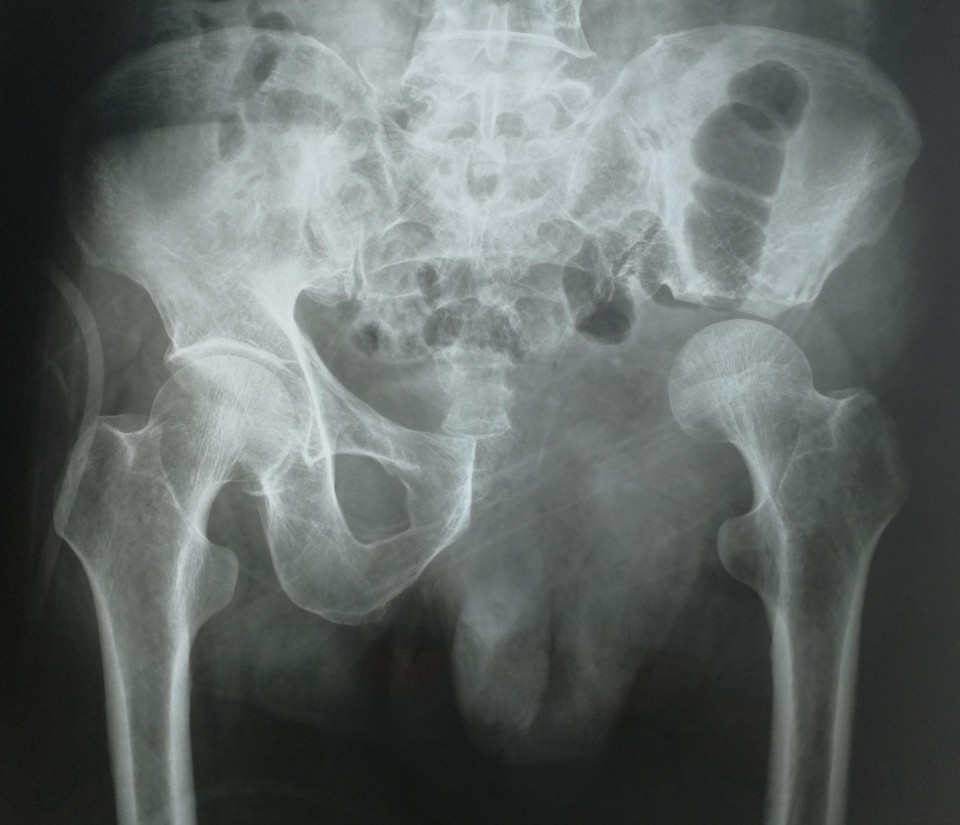

日前,骨病骨肿瘤科近日完成 “骨盆Ⅱ+Ⅲ区巨大软骨肉瘤行内半骨盆切除+股骨头旷置术的保肢治疗 ”1例。患者66岁男性,髋部疼痛不适3月余入院,经检查提示骨盆Ⅱ+Ⅲ区巨大恶性骨肿瘤。骨盆的恶性肿瘤,往往就诊时肿瘤已经发展了相当长的时间,而肿瘤巨大、术中出血多、局部解剖结构复杂等因素使得手术难度及风险增高。早年对骨盆恶性肿瘤的治疗,半骨盆截肢术是骨盆恶性肿瘤的主要治疗方式。但患者所承受的心理压力巨大,面对肢体残缺所引起的恐慌使其拒绝接受治疗,尤其对于年轻患者。保肢术的开展及应用为这些患者带来希望,但手术难度极大,不易达到安全的外科边界。胡勇教授团队根据患者病情,制定精细手术方案,多套手术预案,由于患者经济条件不佳,使用人工关节假体会造成患者极大负担,而且如果出现并发症需要治疗,更导致花费巨大。采用内半骨盆切除+股骨头旷置术,术中既完整的切除了肿瘤,又保全了半侧肢体,辅助术后功能锻炼,几乎可以达到与人工假体相媲美的肢体功能。患者术后顺利康复出院。

胡勇教授指出,骨盆肿瘤的规范化治疗中,肿瘤的完整切除在其治疗中占重要地位,由于骨盆位置深在,血管神经、肠道泌尿道毗邻,骨盆肿瘤的完整切除手术难度极大,技术要求高。对于肢体的重建,虽然人工假体并发症多、价格高昂,但能提供患者相对较好的髋关节功能,肢体长度和外形较满意,故对于大多数患者来说,只要局部软组织重建条件允许骨盆人工关节置换仍是首先考虑的重建方法。该患者由于经济原因不能承受人工假体高昂的费用支出,我们手术尽量保留髋臼顶部骨量,将股骨头置于该处,后期形成假关节可替代原髋关节保留行走功能。一些学者经过长期随访研究,认为旷置成形术避免了很多严重并发症,而且创建了一个无痛且有中等程度功能的肢体。类似骨盆肿瘤的手术我科已开展多例,均取得良好疗效。